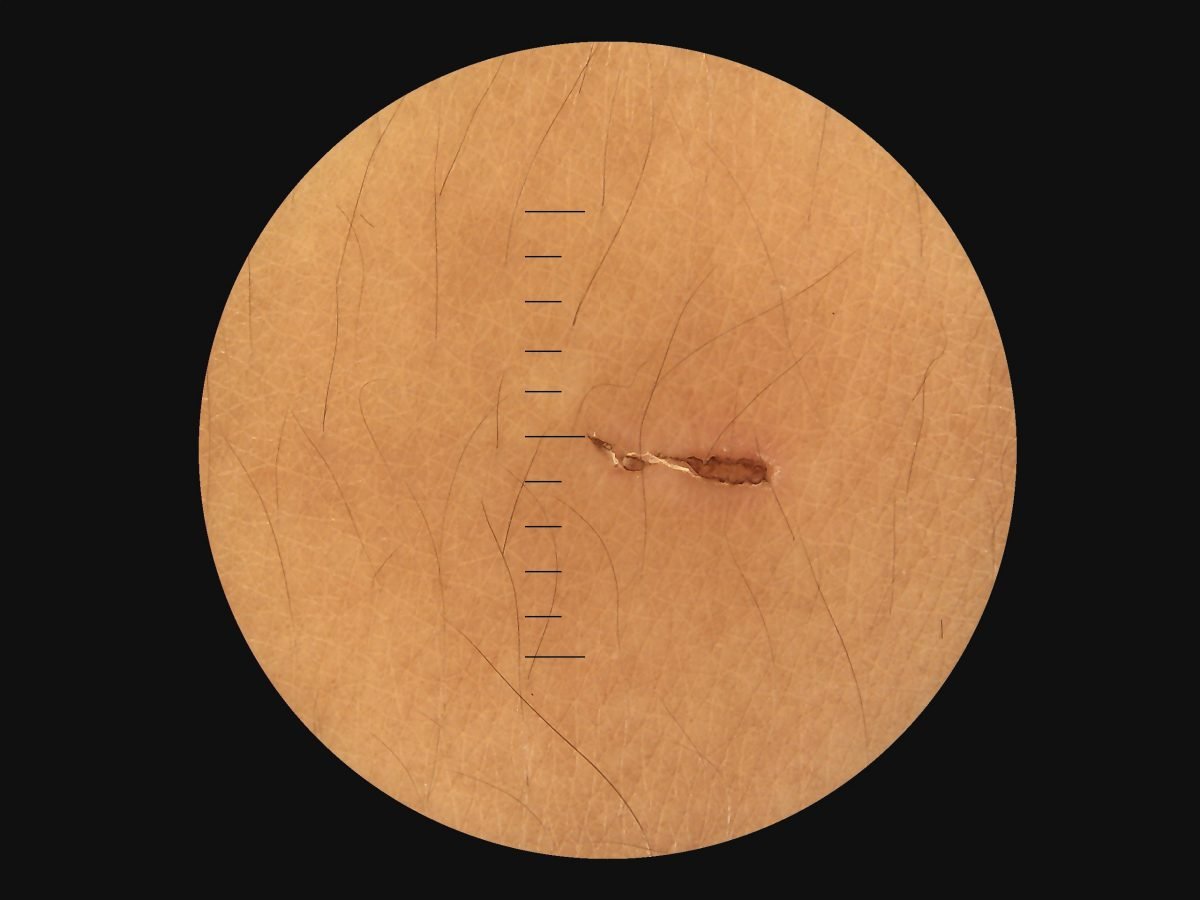

- Provide high definition clinical image

- Portable and hand held application in disease screen

- Multi functional diagnosis in ophthalmology , ENT . Dermatology and general practice.

Image Gallery

Through the scope